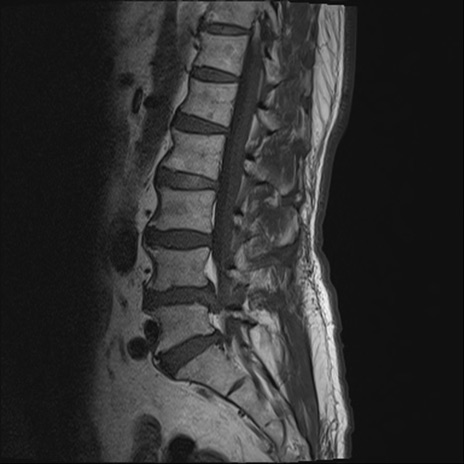

【整形】TIPS症例2 腰椎MRI T1WI(矢状断像)

【症例】70歳代男性

【主訴】左下肢痛

【現病歴】2週間前くらいから腰痛、左下肢痛あり。左臀部から大腿、下腿外側のしびれが常時ある。歩行とともに同部位の痛みあり。

【身体所見】Lasegue70-/60+、Bragard-/±、PTR ±/±、ATR -/-、IP 5/5、TA 5/4、TS 5/5、EHL 右第1足趾なし/3、FHL 5/5、hypersthesia(-)、足背動脈触知良好

異常所見と診断は?